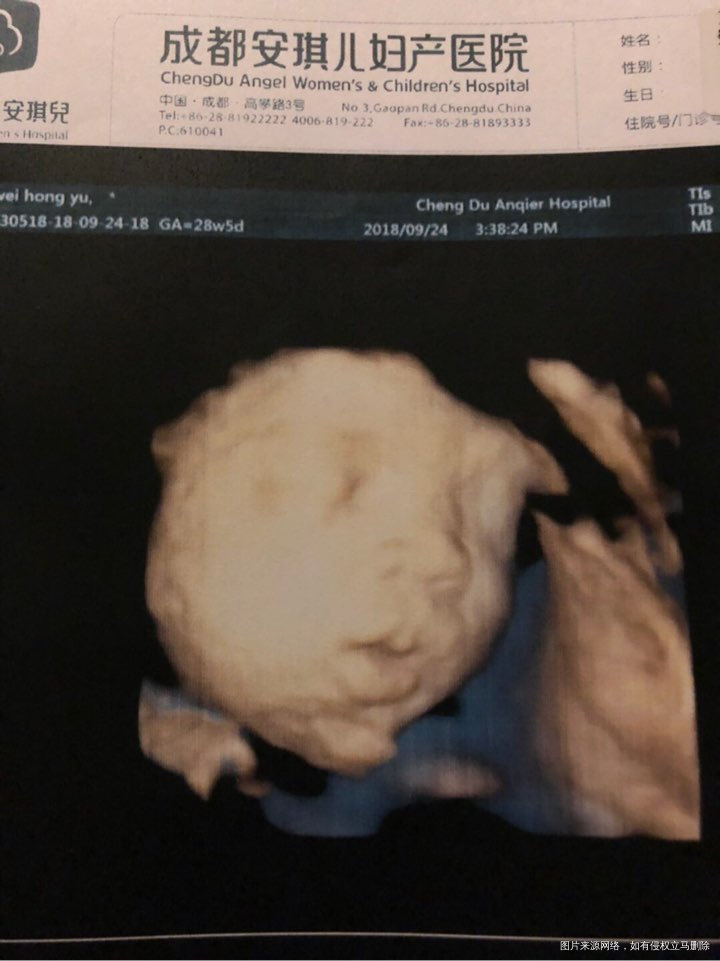

我已经要哭晕在厕所了,宝宝头怎么会这么大啊?股骨才5.7。羊水目前18.6,还是偏高一些。

我觉得这是一个好漂亮的宝宝

想生个狗宝宝 回复 李欣:看样子倒不丑,就是怕脑袋大了不好看😄